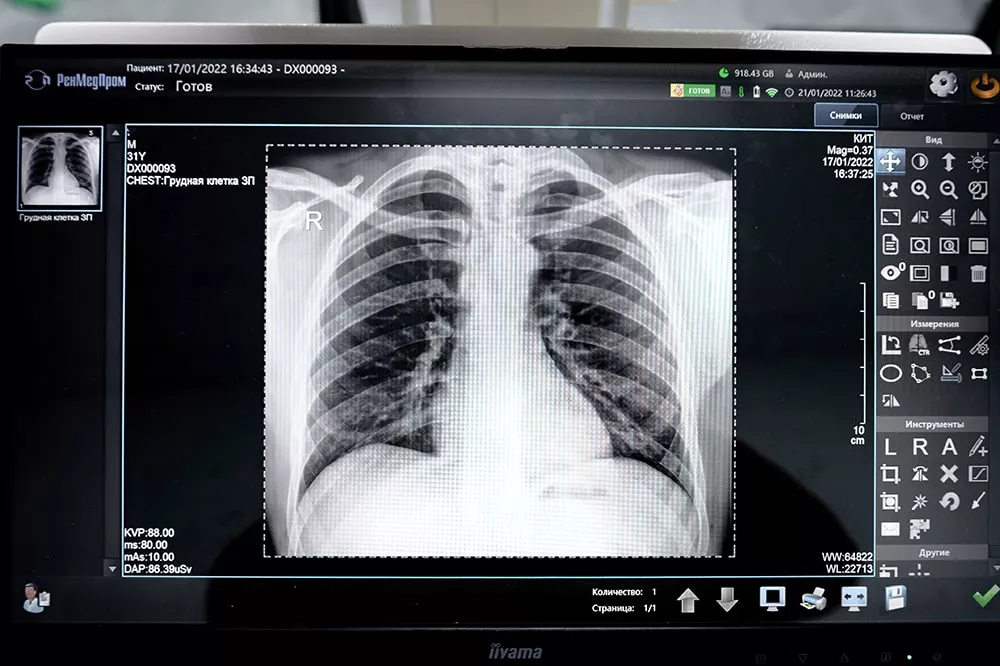

Рентгенография в клинике «КИТ»

Если вам нужна быстрая и качественная рентген-диагностика, обращайтесь в Клинику Ильи Труханова в Куркино. К вашим услугам современное высокоточное оборудование, уютные диагностические кабинеты и опытные специалисты. Наши врачи обладают уникальной базой теоретических и практических знаний в области радиологии. Они проведут быструю и комфортную рентгенографию, интерпретируют результаты исследования и ответят на все ваши вопросы. Точные, детализированные снимки и их грамотная расшифровка позволят врачу поставить верный диагноз и назначить пациенту адекватное лечение.